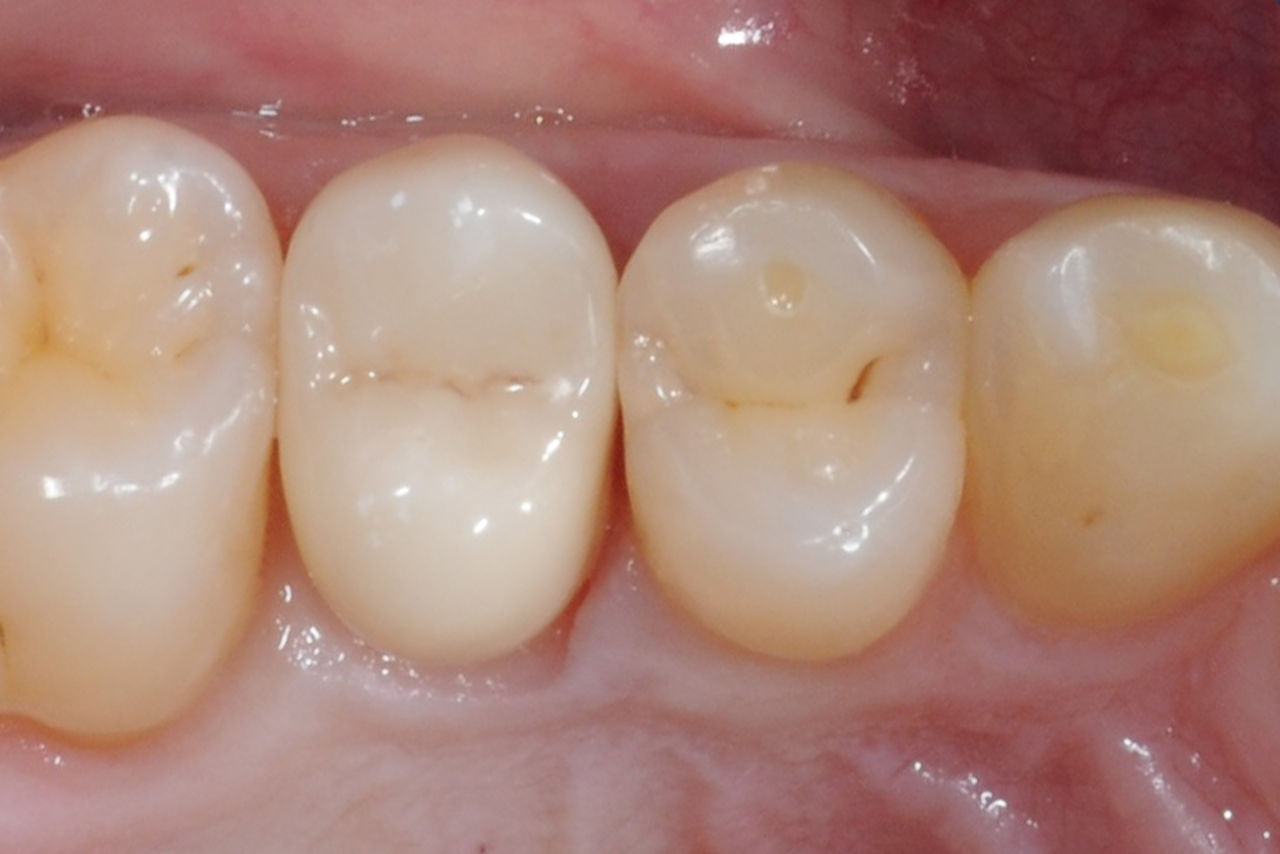

Composite filling, tooth 16, before CEREC treatment

Before

Large insufficiency of the composite filling on tooth 16 with distal marginal ridge cracks, a lingual wall crack and distal recurrent decay.

After

Highly esthetic full-surface glass-ceramic crown.